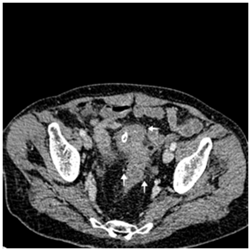

Recto-sigmoidoscopy failed to find the orifice of the fistula. Abdominopelvic computed tomography showed a circumferential thickening of the bladder wall with a posterior parietal collection of 11*16 mm in contact with the sigmoid colon. Uncomplicated colonic diverticula were also revealed (Figure 3−5).

Figure 4 Transversal computed tomography scan showing circumferential bladder wall thickening because of urinary obstruction.

Figure 5 Transversal computed tomography scan showing majoration of bladder wall thickening nearby its contact with sigmoid colon. (Arrow¬)